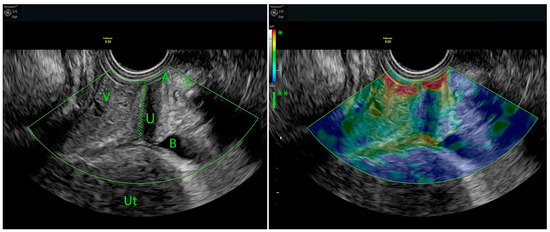

Strain Elastography in Urogynecology: Functional Imaging in Stress Urinary Incontinence

by Lóránt Csákány, Andrea Surányi, Flórián Kovács, Szabolcs Várbíró, Gábor Németh, Attila Keresztúri and Norbert Pásztor

Women 2025, 5(4), 48; https://doi.org/10.3390/women5040048 - 10 Dec 2025

Stress urinary incontinence (SUI) is the most common subtype of female urinary incontinence, affecting up to one in four women and markedly reducing quality of life. Its pathophysiology primarily involves impaired suburethral and paraurethral support, resulting in decreased tissue stiffness and urethral hypermobility. [...] Read more.

Stress urinary incontinence (SUI) is the most common subtype of female urinary incontinence, affecting up to one in four women and markedly reducing quality of life. Its pathophysiology primarily involves impaired suburethral and paraurethral support, resulting in decreased tissue stiffness and urethral hypermobility. Conventional imaging provides anatomical detail but is limited in its ability to assess pelvic floor biomechanics. This narrative review summarizes current evidence on strain elastography (SE) as a functional imaging modality in urogynecology, with emphasis on evaluating suburethral tissue stiffness in women with SUI. A narrative review was performed using PubMed (2000–2025). Primary searches (“strain elastography” AND “female stress urinary incontinence”; “stress incontinence” AND “elastography”) yielded 19 records, of which 12 were included after screening. Owing to the limited number of SE-specific studies, the review was expanded to include shear wave elastography research, key guidelines, and biomechanical literature on pelvic floor ultrasound in adult women with SUI. SE provides a non-invasive, real-time method for assessing tissue stiffness, bridging the longstanding gap between anatomical and biomechanical evaluation. Current evidence supports SE as a feasible and promising diagnostic adjunct for the functional assessment of SUI in women. Full article

Show Figures